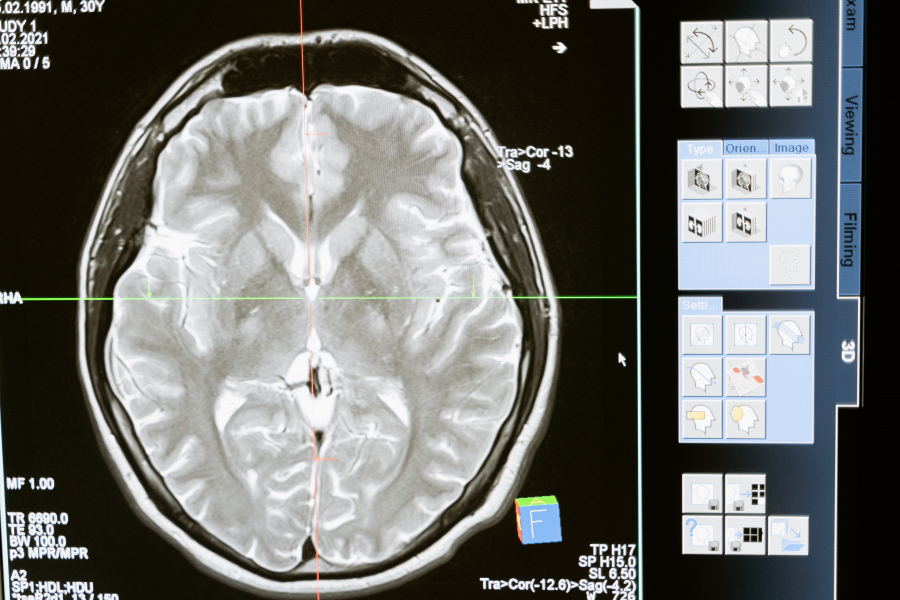

Οι νανοφορείς μπορούν να δράσουν σε όλα τα ζωτικά όργανα του σώματος και να αντιμετωπίσουν οποιαδήποτε ασθένεια μεταφέροντας αδιάλυτα φάρμακα. Διαπερνώντας το φραγμό του εγκεφάλου «μπορούν να αντιμετωπίσουν τον καρκίνο εγκεφάλου ή άλλες νευροεκφυλιστικές ασθένειες», τόνισε η κ. Καραγκιοζάκη, αλλά μπορούν να χρησιμοποιηθούν και από καρκινοπαθείς, «και να κατευθυνθούν σε συγκεκριμένες περιοχές, γλυτώνοντας έτσι τον ασθενή από μια γενικευμένη χημειοθεραπεία που έχει σαν αποτέλεσμα και διάφορες άλλες παρενέργειες».

Είπε, ότι οι νανοφορείς, εκτός της θεραπευτικής του ιδιότητας, μπορούν να είναι και διαγωνιστικοί «δηλαδή να μεταφέρουν ένα διαγωνιστικό μέσο για να αυξήσουμε την ευαισθησία των ήδη υπαρχουσών απεικονιστικών τεχνικών, όπως της μαγνητικής τομογραφίας και των υπερήχων», είπε χαρακτηριστικά.